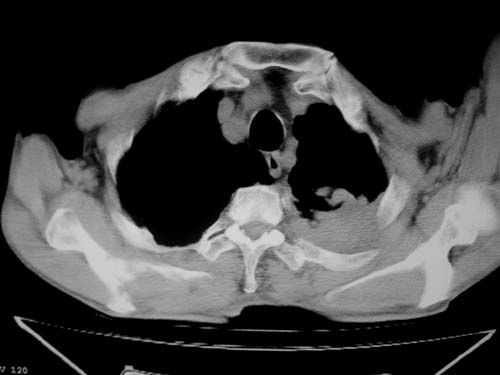

标题: CT19736:男,76岁,咳嗽,胸痛 [打印本页]

标题: CT19736:男,76岁,咳嗽,胸痛

支持左上肺周围型肺癌性并空洞形成伴胸椎转移。

左上沟癌空洞形成并胸椎转移。

支持 左上肺周围型肺癌性并癌性空洞形成伴胸椎转移。

左上肺周围型肺癌性并空洞形成伴胸椎转移。支持

左上肺癌性空洞伴胸椎转移。